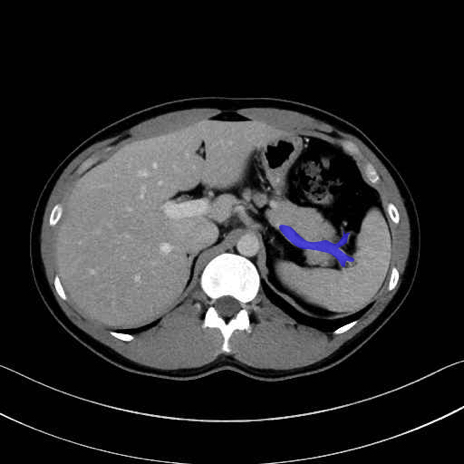

脾静脈の画像解剖

■起始:脾門で脾静脈枝が合流して本幹を形成。

■走行:膵体尾部の後面溝を右走し、膵頸部の後方で上腸間膜静脈(SMV)と合流して門脈を形成。

■主な流入枝:短胃静脈・左胃大網静脈・膵静脈、そして下腸間膜静脈(IMV)(変異あり)。